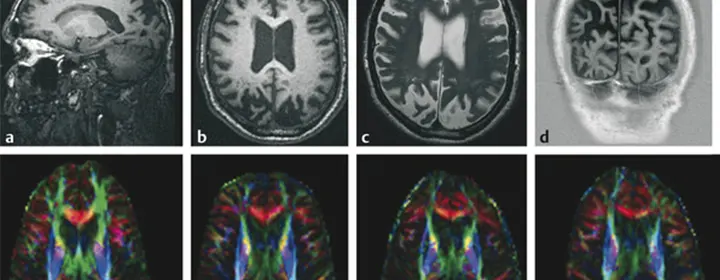

At Keystone Medical Group, we recognize the critical importance of accurate diagnosis in guiding effective treatment for TBI. We utilize state-of-the-art diffusion tensor imaging (DTI), a specialized MRI technique that provides detailed insights into the structural integrity and connectivity of the brain’s white matter. Dr. Buechner, our esteemed interventional neuroradiologist, meticulously analyzes these advanced imaging studies to identify subtle abnormalities indicative of TBI, enabling precise and targeted interventions.

Proper diagnosis is crucial for determining the most effective course of treatment. We utilize advanced neuroimaging, including diffusion tensor imaging (DTI), to identify subtle brain changes and guide individualized therapy plans.